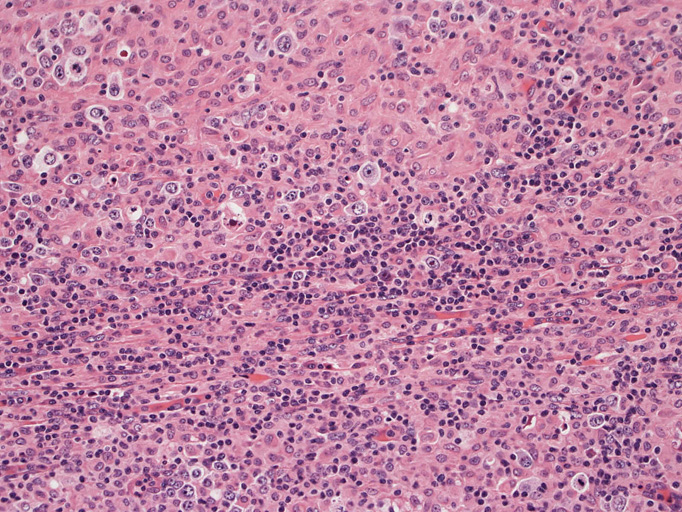

頸部リンパ節病理組織所見

直径17mmの腫大したリンパ節。被膜は軽度線維性肥厚を示す。リンパ節の基本構造は失われ不明瞭な結節様構造が集蔟しているように見える。

結節構造内では, 好酸性細胞質をもつ組織球の増生を背景に大型異型細胞が散在性または集蔟して増殖している。被膜下にも線維化組織内にbizzarreな大型細胞が認められる。リンパ球は小型リンパ球が大型異型細胞を含む組織球性の結節辺縁に存在する。大型細胞は, centroblastic cellが多く, その他 Hodgkin cell-like cell, RS細胞様巨細胞, 腎臓型の核をもった細胞, 多型核の細胞など多彩な形態を示す。異型核分裂像をふくむ核分裂像が多い。

大型異型細胞の形態